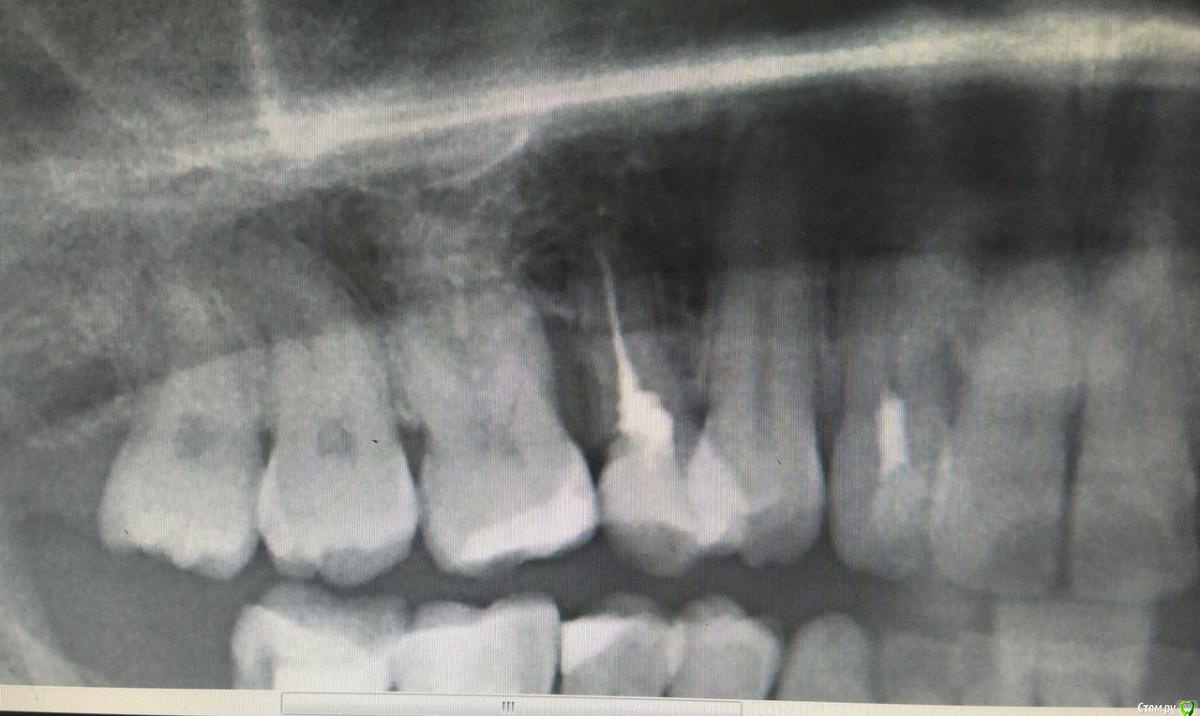

Фотографии начальной ситуации нет, первое фото уже после лоскутной операции и  пересадки  трансплантата с нёба с корональным смещением.

История такая - после ортодонтического лечения с удалением 15зуба образовалась рецессия, которая уходила все дальше и дальше и дальше. В успех мероприятия никто, кроме пациента не верил, первым этапом я отчистила поверхности корней и отполировала нависающие края пломб на контакте, очистила межзубный промежуток, в него только aPRF, натянула, ушила. С нёбной стороны дефект закрылся, отличный сосочек. Вестибулярно стало лучше, но  не фонтан.

Пересадила с нёба лоскут ( на первом фото).Неудачно, частично некротизировался, результат не достигнут.

Отрезала бугор, огромный ломоть, получили толщину тканей феерическую, с избытком таким, что глаз дергался, глядя на этот Эверест (второе фото). Гулять так гулять, подумала я и сделала следующее (на схеме) - расслоила этот бугор, сделав разрез выше края десны, все вокруг деэпителизировала, мобилизовала и натянула. И оно таки сработало! Последнее фото - 6 месяцев результату, продолжаем наблюдать. post-35757-0-84941800-1532674651_thumb.jpgpost-35757-0-82539900-1532674591_thumb.jpgpost-35757-0-09882000-1532674698_thumb.jpgpost-35757-0-47621300-1532674725_thumb.jpgpost-35757-0-64948100-1532674747_thumb.jpg